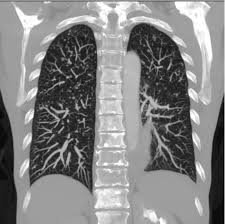

Signs Of Breast Cancer Recurrence In Lungs - P66shca Functions As A Contextual Promoter Of Breast Cancer Metastasis Breast Cancer Research Full Text - More generalized symptoms of cancer, such as fatigue and unintentional weight loss, may also signal a recurrence.. Breast cancer can come back as a local recurrence (in the treated breast or near the mastectomy scar) or as a distant recurrence somewhere else in the body.the most common sites of recurrence include the lymph nodes, the bones, liver, or lungs. When breast cancer moves into the lung, it often doesn't cause symptoms. It can also return and spread to other parts of the body (called metastasis or distant recurrence). Metastatic breast cancer after treatment for early or locally advanced breast cancer (stages i, ii and iii), it's possible for breast cancer to return (recur) and spread to other parts of the body (metastasize). Many of them share symptoms.

Local recurrence is usually found on a mammogram, during a physical exam by a health care provider or when you notice a change in or around the breast or underarm. Many of them share symptoms. Distant recurrence occurs when breast cancer returns in areas further away from the initial site, such as the bones, the lungs, or the brain. Metastatic breast cancer is cancer that's spread from the breasts. The most common sites for breast cancer to spread are the brain, lung, liver and/or.

These are the locations where the recurrence is most often diagnosed. If your breast cancer has metastasized to your lungs, you may not notice any symptoms right away. Symptoms and diagnosis when breast cancer moves into the lung, it often doesn't cause symptoms. If cancer cells are blocking the lymph nodes in. Cancer that comes back after treatment is called a recurrence.but some cancer survivors develop a new, unrelated cancer later. This is the most common type of breast cancer.it begins in. Each person's risk of breast cancer recurrence is different and depends on many factors, such as the size, type, grade and features of the cancer and whether the lymph nodes were affected. Pain or discomfort in the lung This recurrence is also known as metastatic recurrence and cancer travels to the far places in the body like bones, lungs and sometimes even to liver. Pain in your bones, which may get worse when lying down; Symptoms of metastatic breast cancer in the. It causes pain in the bone and chest, continuous dry cough, loss of appetite, nausea and vomiting with severe headaches and fever with chills. Distant recurrence a distant (metastatic) recurrence means the cancer has traveled to distant parts of the body, most commonly the bones, liver and lungs.

The symptoms of a local cancer recurrence are specific to the original cancer. Symptoms and diagnosis when breast cancer moves into the lung, it often doesn't cause symptoms. Download a quick guide to the signs and symptoms of secondary breast cancer. It can also return and spread to other parts of the body (called metastasis or distant recurrence). Breast cancer tends to metastasize preferentially to the bone, lung, liver, spine and larger bones, brain, in that order of prevalence.